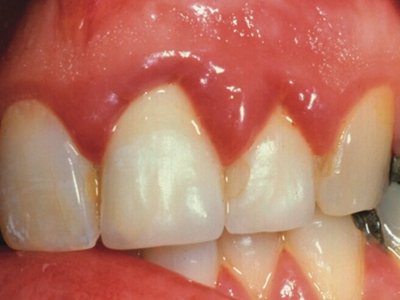

牙龈炎是发生于牙龈组织的炎症,患者可出现牙龈出血伴肿胀、发红、正常形态改变和偶尔不适等症状。本病主要由口腔卫生状况差导致,包括口腔不洁、牙菌斑等,诊断依据临床检查,治疗包括专业牙齿清洁和加强家庭口腔卫生。

牙龈炎可先引起牙齿与牙龈之间的沟(龈沟)加深,然后牙龈充血,炎症围绕一个或多个牙齿,伴牙龈乳头肿胀和易出血。一般无痛,可自行消退,也可维持轻度炎症数年。